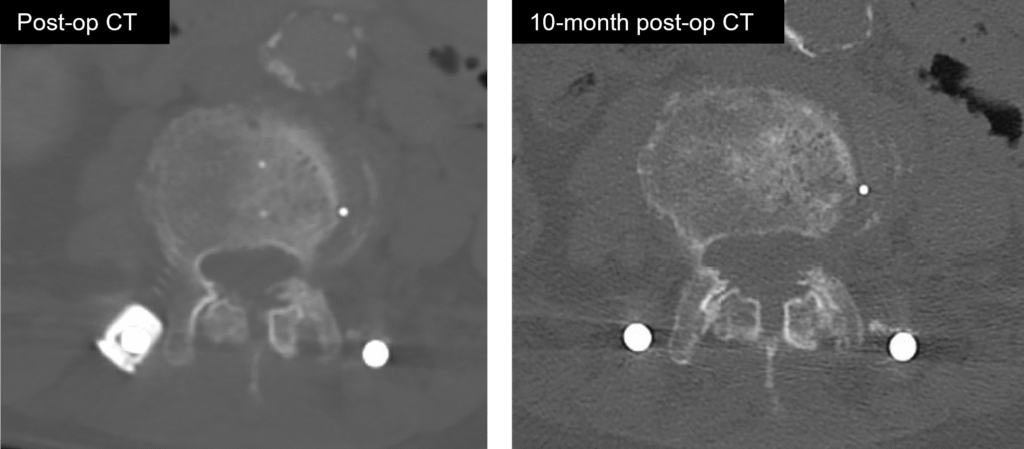

Fuse

FLASH Facet Pellets contain Accell Technology for immediate and sustained release of growth factors4

Post-op CT shows centered decortication

Fusion identified in the facet joint by CT at 10 months